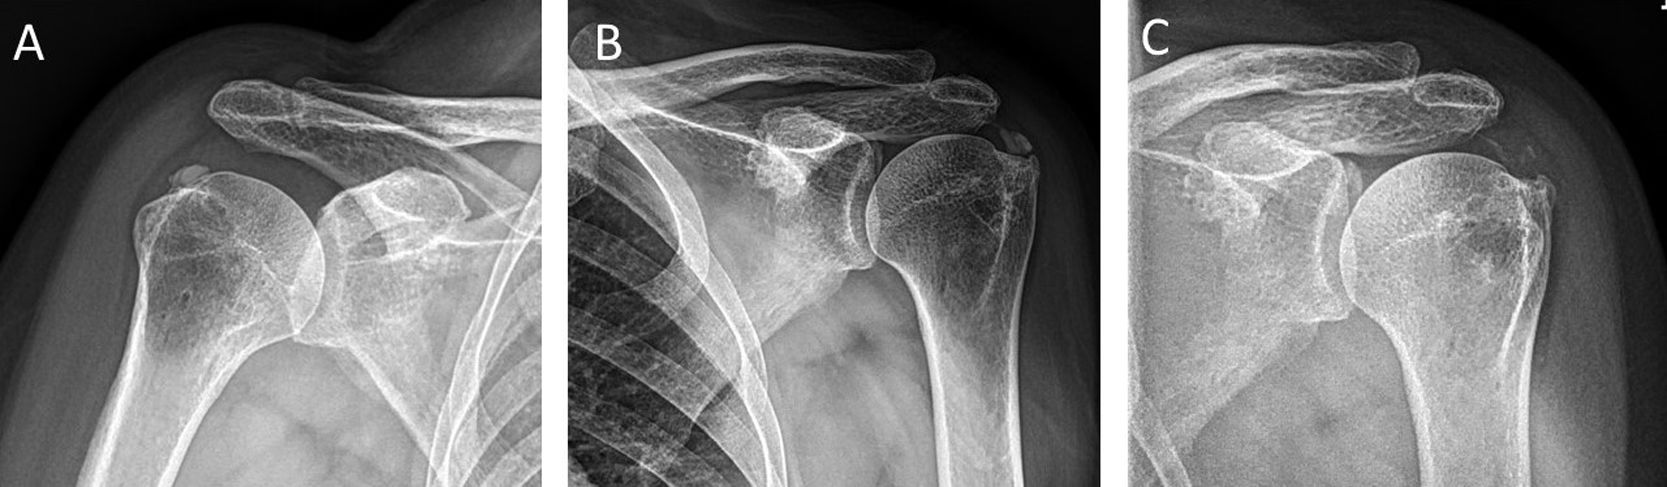

4.2 Chẩn đoán hình ảnh

X-quang (First-line)

• AP vai nội/ngoại xoay

• Xác định vị trí, hình dạng, kích thước vôi

• Phân loại Gärtner

• Dễ thực hiện, rẻ, phổ biến

5.5 Phẫu Thuật Nội Soi (Arthroscopic Surgery)

🔪 Chỉ định Phẫu Thuật

• Thất bại TẤT CẢ điều trị bảo tồn và can thiệp tối thiểu xâm lấn sau > 6 tháng

• Nốt vôi Gärtner Type I rắn, kích thước > 2 cm

• Rách gân bộ phận > 70% độ dày hoặc rách toàn bộ > 2 cm kèm RCCT

• Frozen shoulder nặng kèm RCCT cần giải phóng bao khớp (capsular release)

• Đau dữ dội, VAS > 8 kéo dài, mất chức năng nặng không cải thiện

• Tổn thương đầu dài gân nhị đầu hoặc AC joint cần xử lý đồng thời

Quy trình phẫu thuật nội soi:

Portals: Portal sau 2 cm dưới góc sau-ngoài mỏm cùng vai → nội soi vào khớp → portal trước ngoài coracoid. Nội soi khớp ổ chảo đánh giá mặt khớp gân trước → chuyển sang không gian dưới mỏm cùng → cắt bỏ SA bursa rộng rãi (bursectomy) → định vị ổ vôi bằng kim 18G xuyên qua gân từ ngoài vào → rạch nhỏ bằng dao mổ nhỏ theo trục dọc gân → nạo và hút sạch canxi.

Có cần sửa gân sau lấy vôi không?

Bằng chứng hiện tại: Nếu khuyết gân < 2 cm và < 70% độ dày → không cần sửa gân, để tự lành. Nếu khuyết ≥ 2 cm × 1,5 cm hoặc > 70% độ dày → cần sửa gân (suture anchor tại điểm bám; side-to-side sutures tại musculotendinous junction). Khoảng 26,5% bệnh nhân cần sửa gân sau lấy vôi nội soi.

Có cần acromioplasty đi kèm không?

Còn tranh luận. Molé và cộng sự nhấn mạnh vai trò acromioplasty với nốt vôi nhỏ. Tuy nhiên Jacobs & Debeer (2006) không tìm thấy sự khác biệt có ý nghĩa giữa nhóm có và không có acromioplasty. Xu hướng hiện tại: chỉ acromioplasty khi có bằng chứng impingement thực sự.

🖼 Hình 11 – Phẫu thuật nội soi: lấy vôi và sửa gân

A: MRI trước mổ. B: Quan sát nội soi sau bursectomy. C: Nạo vôi. D: Sửa gân bằng suture anchor

Phẫu thuật nội soi lấy vôi và sửa gân